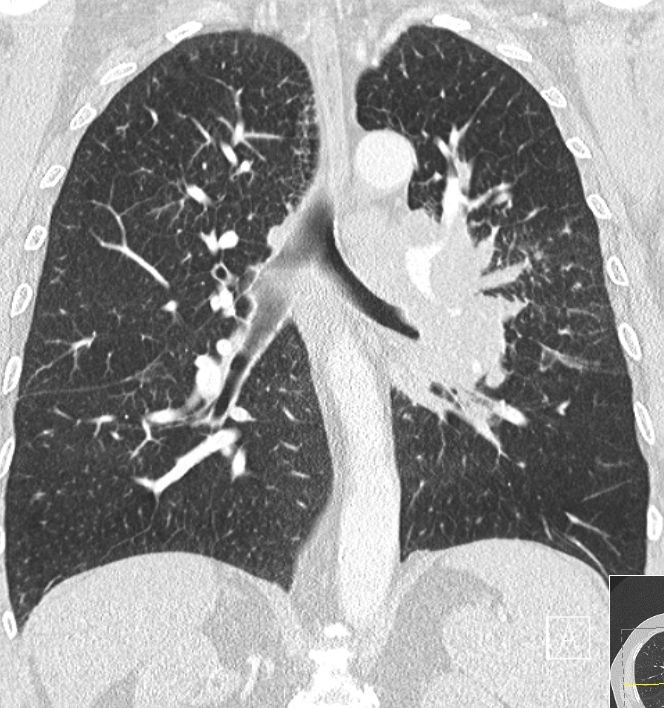

zentrales, kleinzelliges Lungenkarzinom rechter OL mit Infiltration des Mediastinums T4 N3 M1 oss ? 68jährige Patientin im reduzierten AZ und normalen EZ. Unsicherer Gang bei Kreislaufstörungen. Belastungsdyspnoe. Deutliche Leistungsschwäche. Supraklavikulargruben: links frei, rechts auffälliger Tastbefund. ![]() |

![]() |

![]() | ||

![]() | ||||